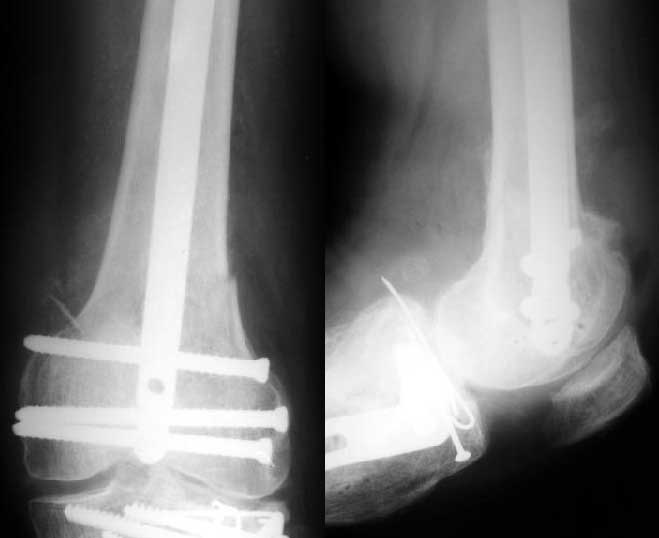

I do not see the proximal bolts; I presume they must be at he trochanter level. In a supracondylar nail you are able to see both side bolts in one picture. ( Enclosure)